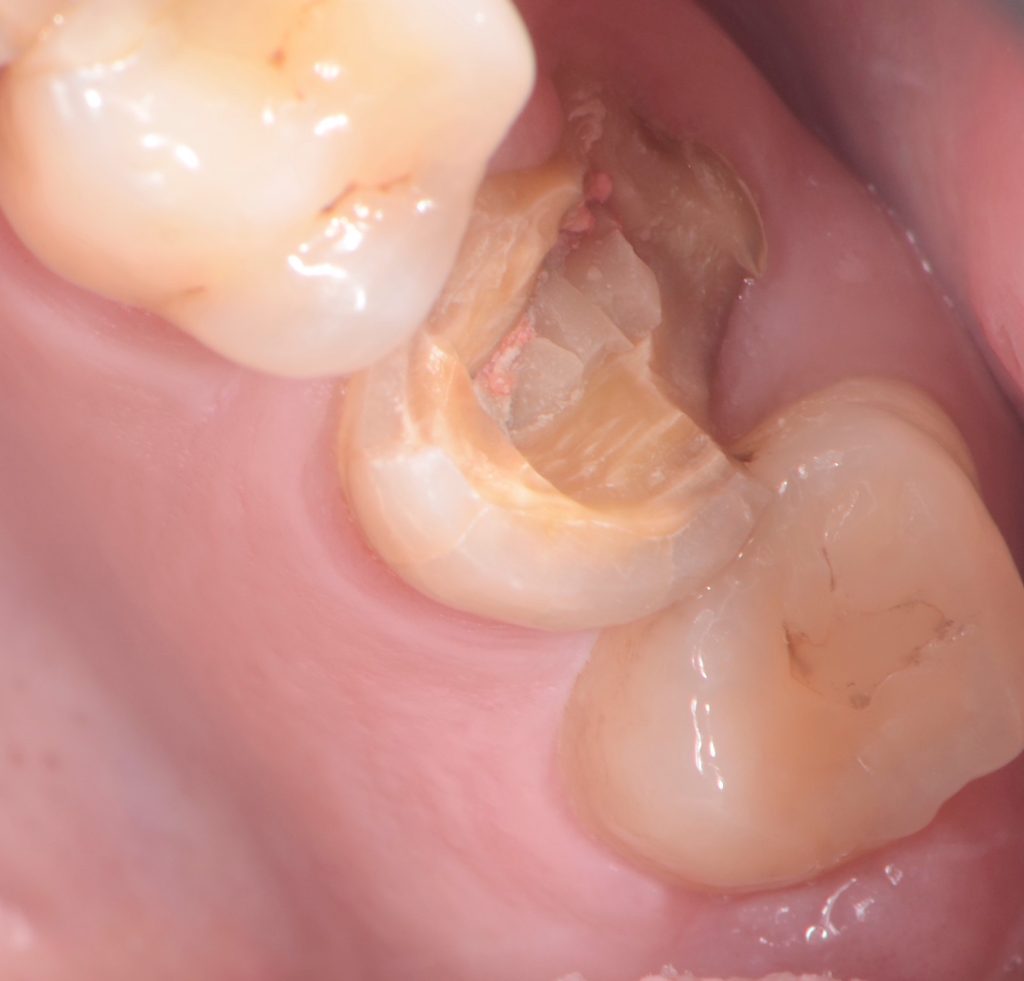

Fatigue is the breaking or fracturing of a material caused by repeated cyclic loads below the yield limit. Intraoral occlusal forces create this dynamic repetitive loading; thus, instead of a monotonic static load to fracture, normally patients experience a physiologic fatigue load. (Figs. 1-2)

Fatigue life is defined by the number of load cycles required for a specimen to fail for a given applied load. This number relies on several variables, such as stress level, stress state, cyclic wave form, fatigue environment and metallurgical condition of the material. However, fatigue life may also refer to a preliminary failure condition as opposed to complete fracture of the specimen.

The same is found with a fracture of a cusp or fragment of a tooth that has an intra-coronal restoration, such as an inlay, an amalgam, or a composite resin. (Figs. 5-6)

Fatigue cracks initiate and propagate in regions where the strain is most severe. This area of high deformation initiates a fatigue crack, which propagates under the applied stress through the material until the complete fracture, which once again may very well be evidenced for the first time while chewing sticky or soft food.